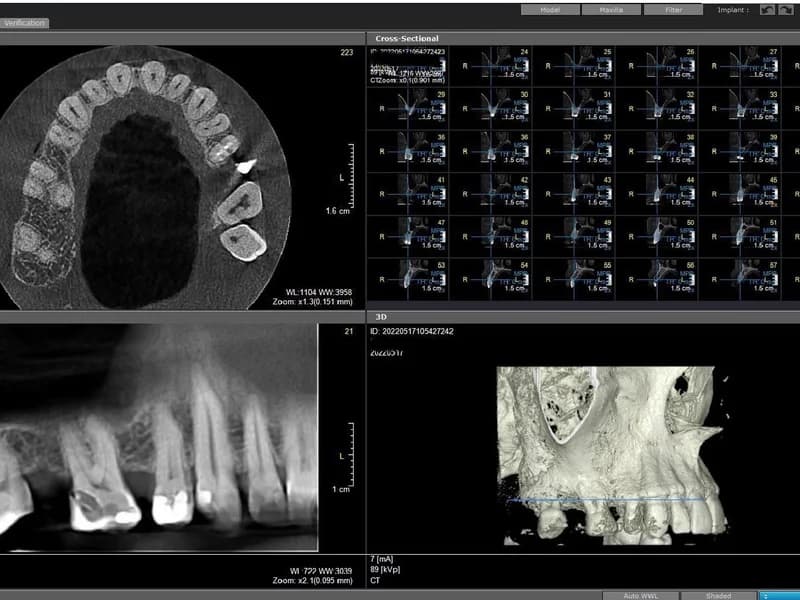

- –CBCT snimanje zubi(Najprecizniji oblik dentalnog snimanja koji omogućuje trodimenzionalni prikaz zuba, kosti i okolnih struktura. Koristi se najnovija digitalna CBCT tehnologija s niskom dozom zračenja i iznimnom rezolucijom. Precizan prikaz do 0,01 mm, veliko polje snimanja (do max. 20x17 cm).)